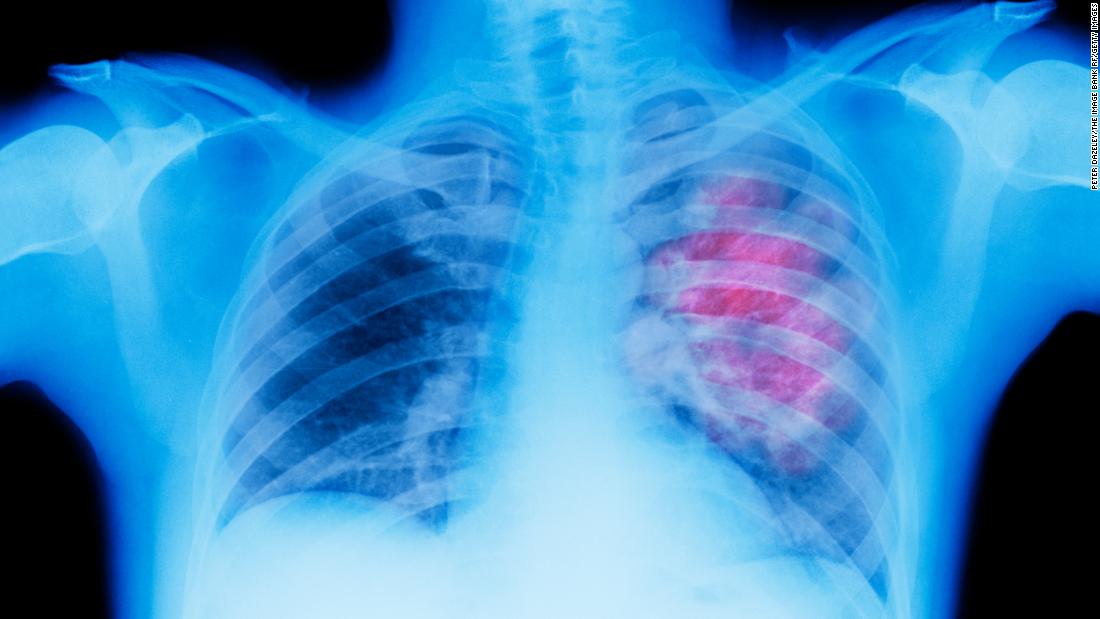

Los principales cánceres en términos de muertes atribuibles a los factores de riesgo a nivel mundial en 2019 fueron el cáncer de tráquea, bronquios y pulmón tanto para hombres como para mujeres, hallaron los investigadores.